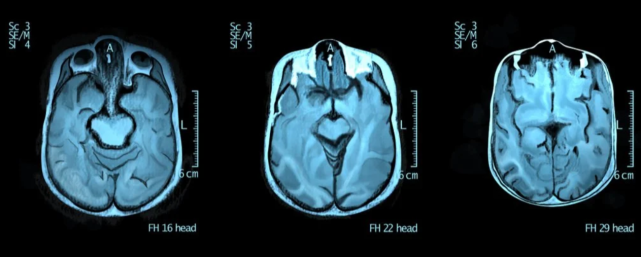

图注:自闭症患者的大脑更加对称

我们的思维和认知过程在左右脑之间来回穿梭,而闭症患者大脑左右两边的交流有点困难,或者两边没有那么多紧密联系。

另外,自闭症患者大脑的灰质和普通人也不太一样,大脑的灰质越多,则意味着可以处理的信息就越多,而有些自闭症患者会在某些区域灰质突然显著增多,这可能是他们变成某方面“天才”的原因。